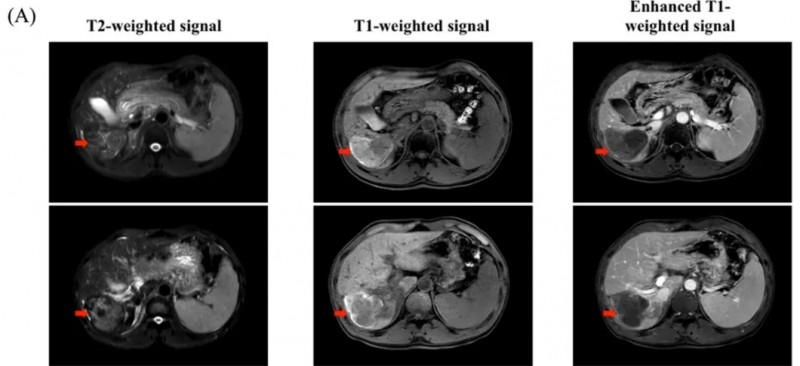

《新英格兰医学杂志》曾报道过一个“应用靶向野生型EGFR及EGFRv III的CARv3-TEAM-ET细胞,治疗复发性胶质母细胞瘤(GBM)”的惊艳案例(NCT05660369)。

该患者是一位57岁女性,因数周词汇困难及癫痫发作就诊,MRI示左顶叶强化肿块。开颅术后病理确诊为IDH野生型、MGMT未甲基化GBM,伴EGFRvIII阳性及EGFR拷贝数增加。放化疗后影像学提示肿瘤复发,遂入组通过脑室内导管接受CARv3-TEAM-ET细胞治疗。

结果显示:输注前MRI可见广泛复发病灶,输注后第5天MRI示肿瘤几乎完全消退(详见下图);治疗后脑脊液细胞外囊泡RNA中EGFRv III及EGFR拷贝数先降低,后均无法检测。